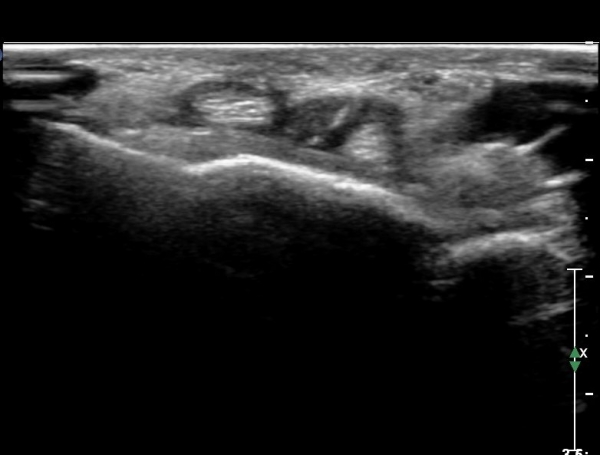

Å½ÃËÀÚ¸¦ ¾à°£ ³»ÃøÀ¸·Î À̵¿ÇÏ´Ï FPL ÈûÁÙÀÌ °íÁ¤¹°¿¡ ÀÇÇØ ¾Ð¹ÚµÇ°í ÀÖÀ½ÀÌ È®ÀÎµÇ°í ±ÙÀ§ºÎ¿Í ¸»´ÜºÎ´Â

Àú¿¡Ä¿ ºÎÁ¾ÀÌ °üÂûµÇ°í ±× »çÀÌ´Â °¡´Ã¾îÁ®¼­ ÈûÁÙÀÇ ¼Ò½Ç(ÆÄ¿­)À» ÃßÁ¤ ÇÒ ¼ö ÀÖÀ½(»çÁø 10. 11)